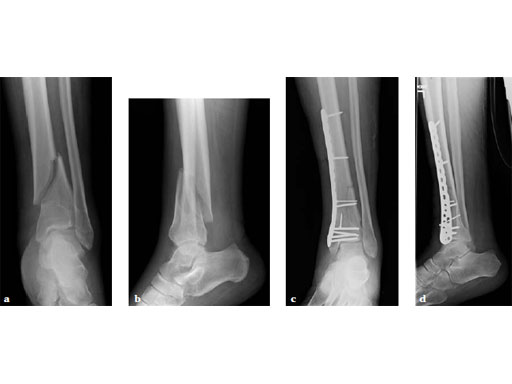

75-year-old male, post motor vehicle collision with ipsilateral split depression lateral tibial plateau fracture.

Case provided by Matthew Graves, Jackson, USA